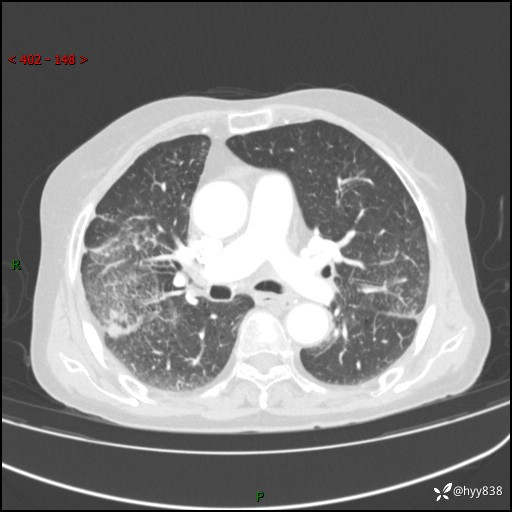

胸部CT增强(外院平扫)